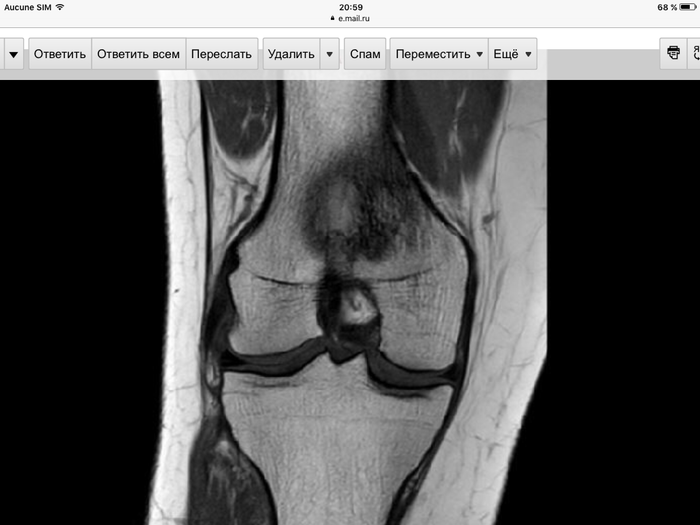

Помогите распознать болячку.

В свете постов про врачебные/ неврачебные ошибки.

Имеется : лишний вес в кол ве 10-15 кг

Тянущие боли на задней поверхности ноги от продолжительных сидения/лежания/ стояния/ хождения

Опухание области колена после плавания

Очень интересный симптом : после принятия противовоспалительного флектора ощущается "движение" под коленной чашечкой.

Травм колена в обозреваемом прошлом не было

Назначены допплер И ирм. Допплер ничего не показал, ирм показал что то (? )в кости.

Если честно кость не так волнует как опасность промухать что то типа тромбоза или хз чего ещё .

На сегодня прописано замещающим доктором ибуфетум и хондропоротектор который воняет тухлой рыбой.

PS интернет на заданные симптомы выдаёт много диагнозов, пугает и запутывает ещё больше.

Ну и вот она самая коленка. Ирм.